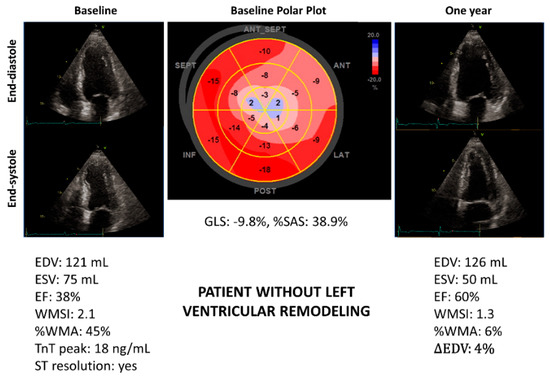

3.3. Primary Objective: Left Ventricular Remodeling